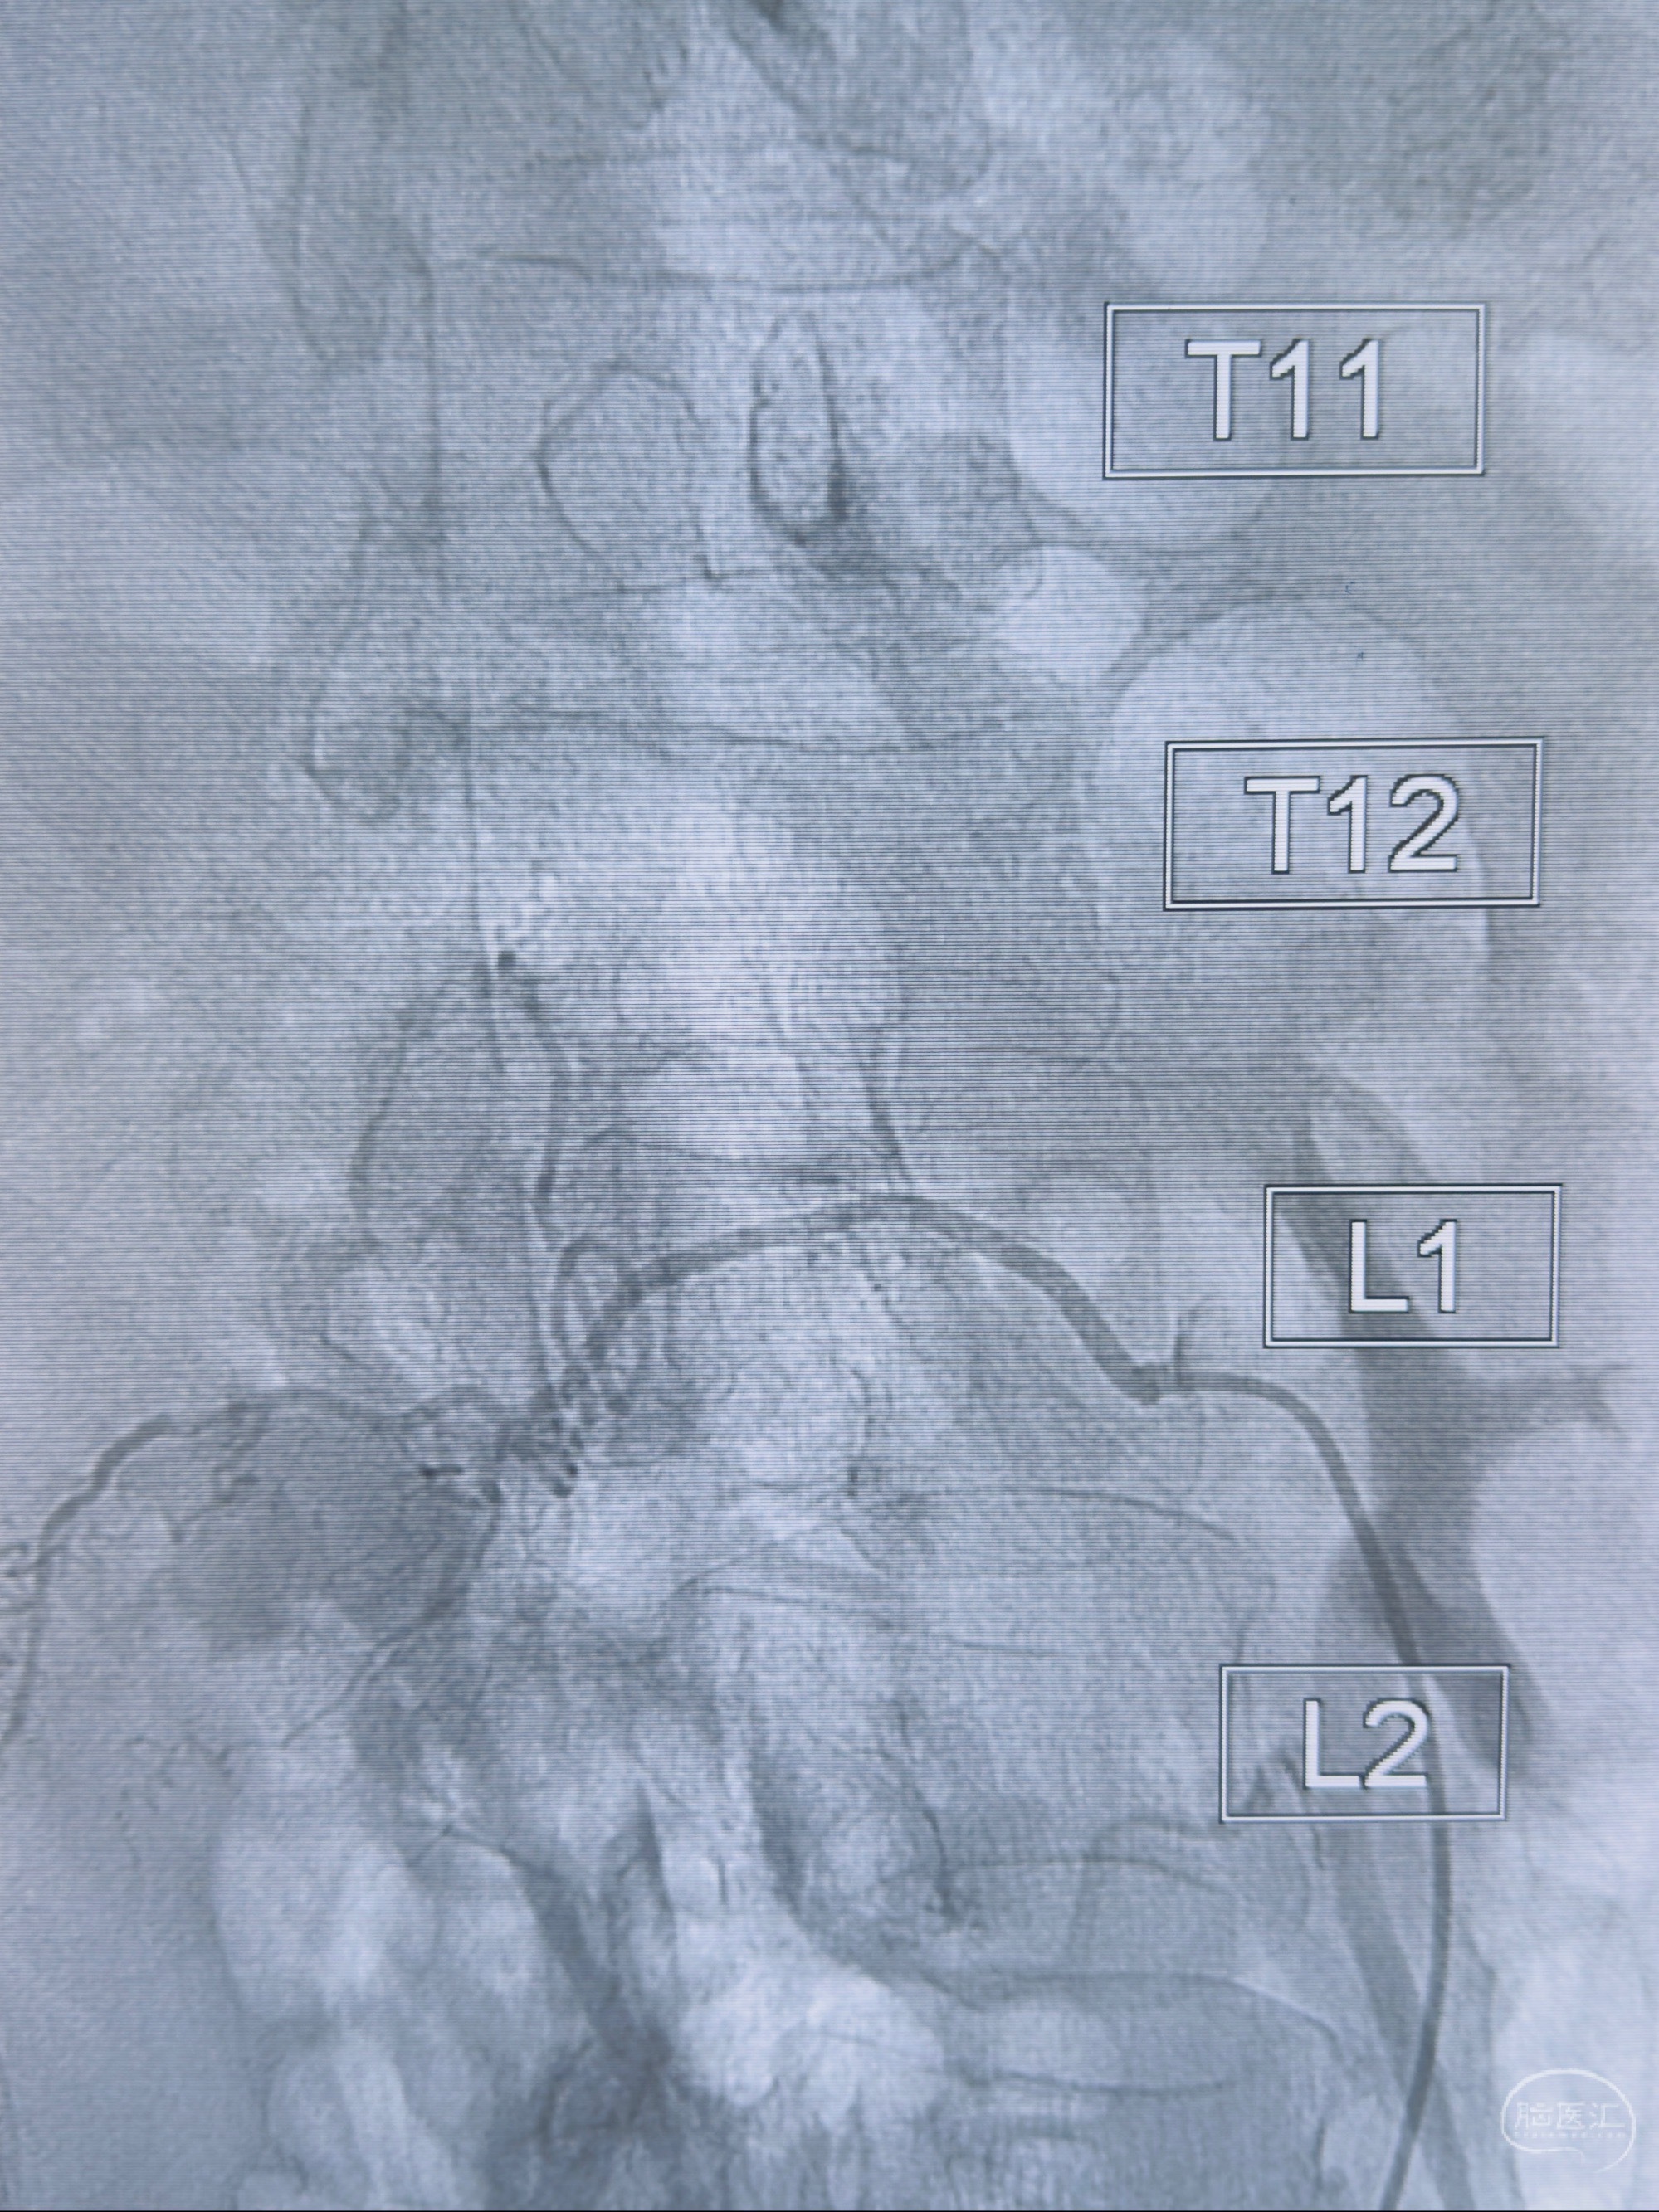

2023-10-13DSA:右侧L1水平硬脊膜动静脉瘘,供血动脉为右侧L1,附近动脉未见明确吻合供血,供血动脉处可见脊髓前动脉发出